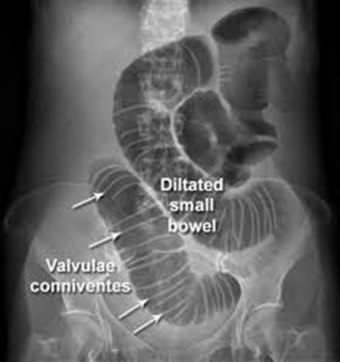

What CT finding distinguishes jejunal loops from other small bowel segments?

Valvulae conniventes - parallel lines visible within the lumen representing circular folds. These are most prominent in jejunum and help identify the segment.